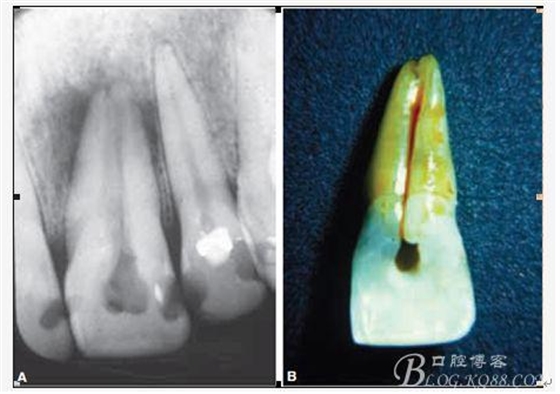

D、牙根的內(nèi)外吸收 這個(gè)目前具體機(jī)制也不是非常明確,只要能想到這個(gè)層面,通過(guò)X片檢查不難發(fā)現(xiàn),尤其到了有臨床癥狀的時(shí)候;

E、牙齒本身的畸形與缺陷 常見(jiàn)的比如下5的畸形中央尖以及切牙的舌側(cè)窩、深及根尖區(qū)的舌側(cè)溝或者牙中牙等等;